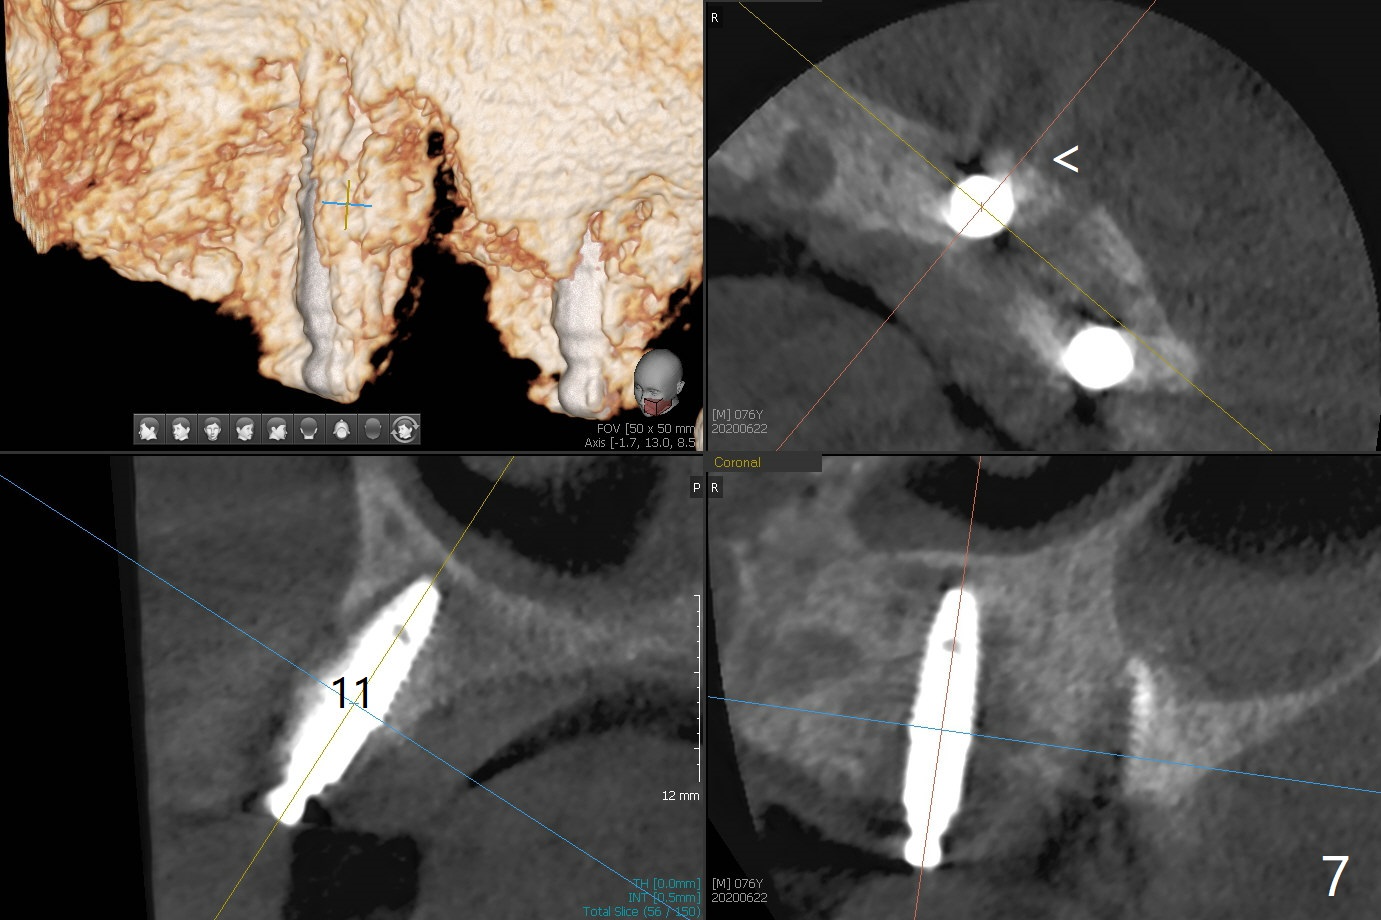

Osteotomy at #13 starts blindly (no incision or tissue punch) with bone expanders. After insertion of parallel pins, intraop CT shows that it is palatal with apparently buccal low bone density (Fig.1); the osteotomy for implant (Fig.2 green) should be shifted buccal and tilted mesial (red, parallel to #11) with incision. In contrast the position, trajectory and depth (Fig.3 <) of the initial osteotomy are acceptable at #11. The implant will be placed as it is (Fig.4). After taking a postop PA (Fig.5), the implant at #11 is placed a little deeper to make sure its slightly subcrestal placement (including distal incision at #11). Following placement of 3.5x4 and 3 mm ball abutments at #11 and 13, cortical allograft with PRF is placed around the implants, especially buccal (Fig.6,7 <). After suturing, the profile of the ball abutments is too low for RPD retention. Due to gravity other than bone density, the number of ball abutments for the maxilla should be more than for the mandible. Soft reline is done to the patient's satisfaction. The retention of the upper RPD after soft reline is satisfactory without pain 7 days postop (Fig.8). The implant at #13 is loose nearly 3 months postop (Fig.9 *: bone loss). The implant is removed while the ball abutment is untightened; the sinus floor is present. It appears that a longer and larger implant is necessary; a 4.5x10 mm dummy implant is unable to be seated deep or achieve primary stability (Fig.10). After sinus lift with 3 mm Bicon osteotome without bone graft, the dummy implant accomplishes the 2 tasks mentioned above (Fig.11). However there is no corresponding definitive implant in stock. Implant system needs to be changed; with a change in implant driver, the depth control is lost. The final implant is placed deep (Fig.12). With back up, stability is lessened; a healing screw is placed; with collagen plug, the wound is sutured (Fig.13). The wound heals 1 week postop (Fig.15). The RPD is soft relined. Retention from the ball abutment at #11 is apparently critical. The RPD and #11 implants (4 months postop) are stable, while the wound at #13 heals 1.5 months postop (Fig.15). There is space around the implant 5.5 months postop (Fig.16 *). The 5x10mm SM implant is found to be loose upon uncover and removed. After debridement, 5.3x8 mm SM and 5.5x9 mm IBS dummy implants are inserted without stability, while 6x9 mm definitive one with stability (Fig.17). Cortical allograft is placed in deficiency areas (*). The osteotomy has no roof (sinus floor), but the sinus membrane is intact. Small amount of bone graft (Fig.18 *) is placed before implantation. There appears to be bone around the new implant (Fig.19 (3D sagittal section) *).